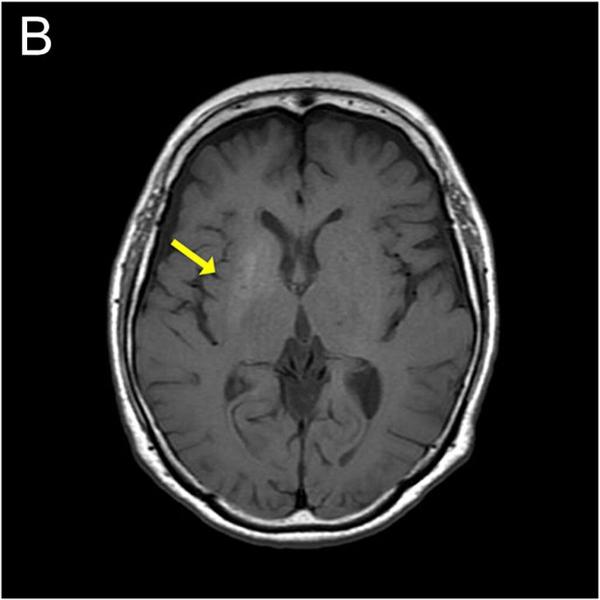

Accelerated hypertension is a medical emergency featuring a rapid, severe rise in blood pressure (often more than 180/120

mmHg) that causes acute damage to target organs, particularly the eyes, kidneys, or brain

. Symptoms include severe headaches, blurred vision, chest pain, and confusion. Immediate, controlled medical treatment is necessary to prevent permanent injury or death.

Definition & Characteristics: It represents a sudden acceleration of blood pressure in a patient with chronic hypertension. Unlike malignant hypertension, which presents with papilledema (swelling of the optic nerve), accelerated hypertension involves retinopathy (flame-shaped hemorrhages, exudates) without it, though both are treated as hypertensive emergencies.

Target Organ Damage: The rapid rise in pressure leads to acute organ failure, such as impaired kidney function (indicated by proteinuria or increased creatinine).